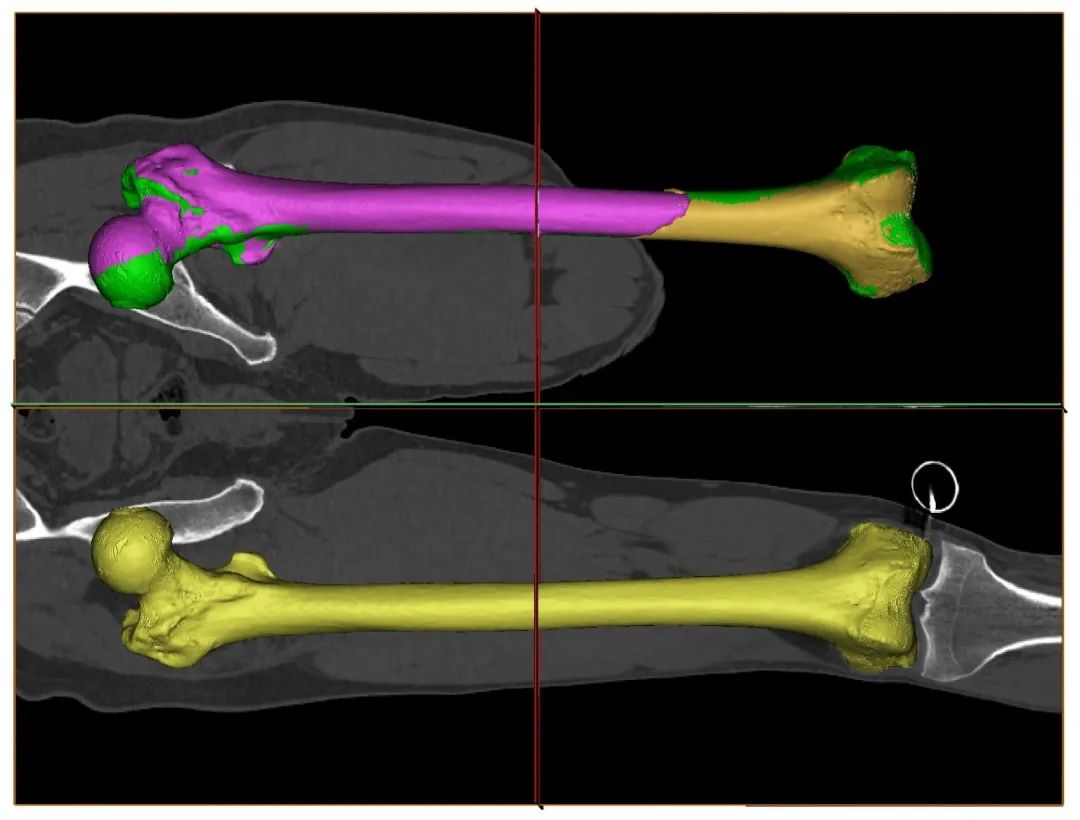

术前,吴新宝副院长带领团队进行了周密的准备,基于患者的术前影像,利用计算机与健侧肢体完成镜像配准,实现了个性化、定量化的复位规划。

复位规划

术中,创伤骨科赵春鹏主任医师作为主刀医生,通过术前与术中影像配准实现对股骨近端及远端的实时三维追踪导航,在三维导航下植入把持针,而后使用机械臂稳定把持股骨近端,使用骨盆骨折复位机器人自动完成骨折复位,术中透视验证复位精准满意。